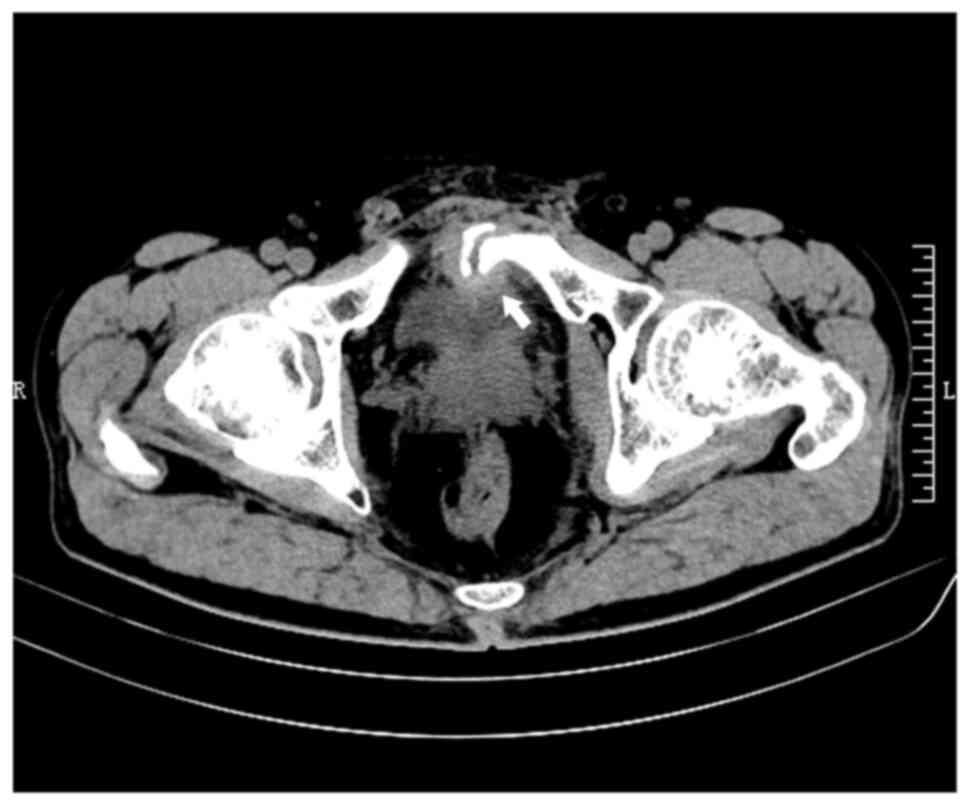

Secondary bladder stone caused by delayed penetration of the bladder by a pubic fracture: A case report and literature review

Pelvic fractures sometimes lead to injuries of the urinary bladder, which commonly present as gross hematuria, dysuria and lower abdominal pain. As a type of urinary stone, bladder stones are usually secondary to lower urinary tract obstruction, such as benign prostatic hyperplasia, urethral stricture, and neurogenic bladder. The present case report examines an unusual case of a delayed pubic fracture penetrating the bladder, which caused a secondary bladder stone. A 53-year-old man was first hospitalized at The Second Hospital of Jiaxing (Jiaxing, China) in January 2020 because of trauma-induced bleeding in the scalp and abdominal pain. The patient underwent abdominal exploration and partial bowel resection, and his condition stabilized after surgery. After discharge, the patient had regular outpatient check-ups every 2-3 weeks. However, after 3 months, in April 2020, the patient was readmitted to the hospital because of frequent urination, an urgent need for urination and dysuria. Abdominal computed tomography imaging and cystoscopy revealed a pubic fracture that had penetrated the bladder wall, accompanied by a bladder stone. Subsequently, cystolithotomy was performed, which provided significant relief of symptoms once the catheter was removed after 2 weeks. Since then, the patient has been followed up until January 2023 and had remained asymptomatic. Bladder stones caused by necrotic bone fragmentation are rare. Bladder injuries resulting from pelvic fractures can have delayed onset; therefore, clinicians should be aware of the possibility of urogenital injury in such patients. It is crucial for clinicians to comprehend the potential mechanisms involved, analyze the clinical data of patients, closely monitor their condition and implement appropriate treatment measures when necessary.